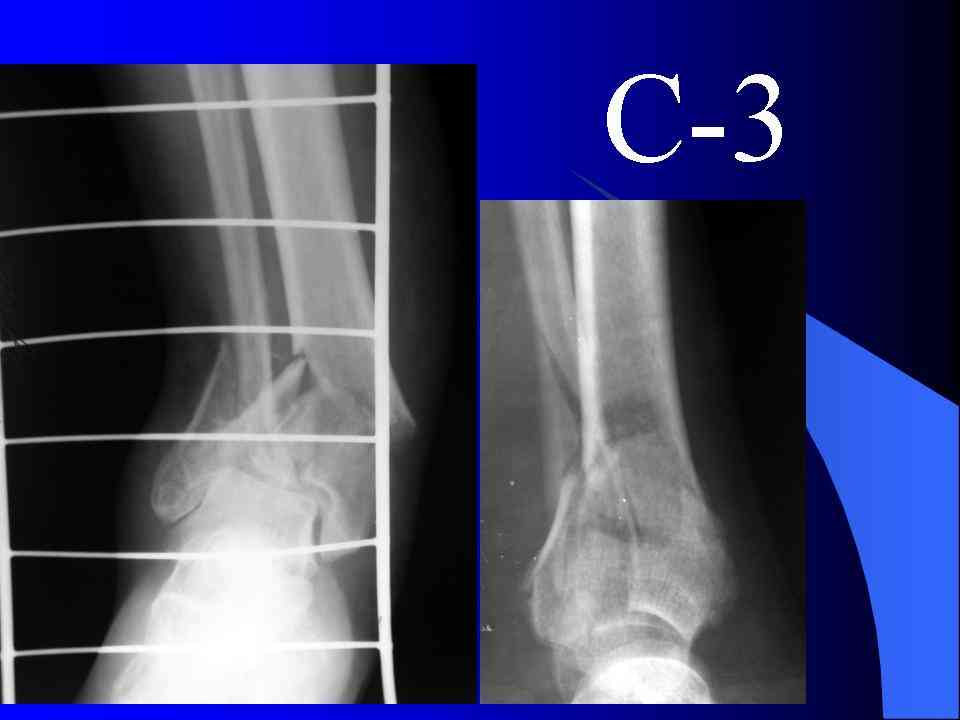

На рентгенограммах типичный перелом пилона по типу С-3. есть опыт до 100 открытых опреаций у нас в клинике. 20 примерно в год. Принцип один -все внутрисуставные переломы нуждаются в открытой репозиции и внутренней стабильной фиксации. При поступлении КТ не надо, так как получается только нагромождение костей. Истинной картины нет. Главное восстановить длину малоберцовой кости - это ключ к успеху. При поступлении меньше всего надо думать о сосудистых расстройствах, т.к. сама операция и репозиция даже сначала частичная даёт улучшение сосудитых нарушений. Причём очень быстро. Операция в 2этапа. При поступлении доступ позади наружной лодыжки, причём обязательно. После этого репозиция малоберцовой кости и фиксация пластиной 1/3 трубки под винт 3,5. Дренаж и любой аппарат наружной фиксации. Затем после спадения отёка на 5-7-10 день аппрат снимается и дугообразный разрез спереди от медиальной лодыжки 10-12 см. Главной чтобы расстояние между 1 и вторым разрезом было не меньше 7-8 см. Тогда не будет некрозов лоскутов. Таранная кость используется как матрица на неё укладываются отломки и фиксируются пицами. Ренг-контроль. Отломки лежат все отдельно, но ничего не высыпется. При переломах С-3 всегда нужна костная пластика (из крыла). Фиксация пластиной лист клевера простой или LCP. Гипс не нужен. Дренаж до 48 часов. Операция длится 3-4 часа обязательно без жгута. Посылаю примерно такой же случай.

Послала ещё два снимка, если не пройдут, пошлю ещё. Дрягин. Если есть вопросы, готов ответить.